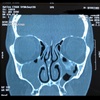

Dx

Sinusitis